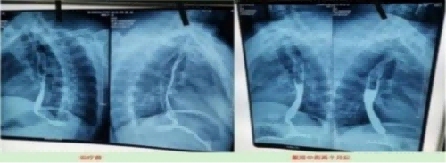

案例7、食道癌两个月清零

患者:刘喜良 男 46岁 食道中段癌

2023年10月9日CT影响报告诊断查出食管壁增厚,管腔狭窄,食管癌。找到陈海林老师使用中医药两个月治疗后CT显示食管各段顺利通过,食管恶性肿瘤治疗后改变。

上图是服用两个月中药的前后对比图

上图是服用两个月中药后检查报告对比图